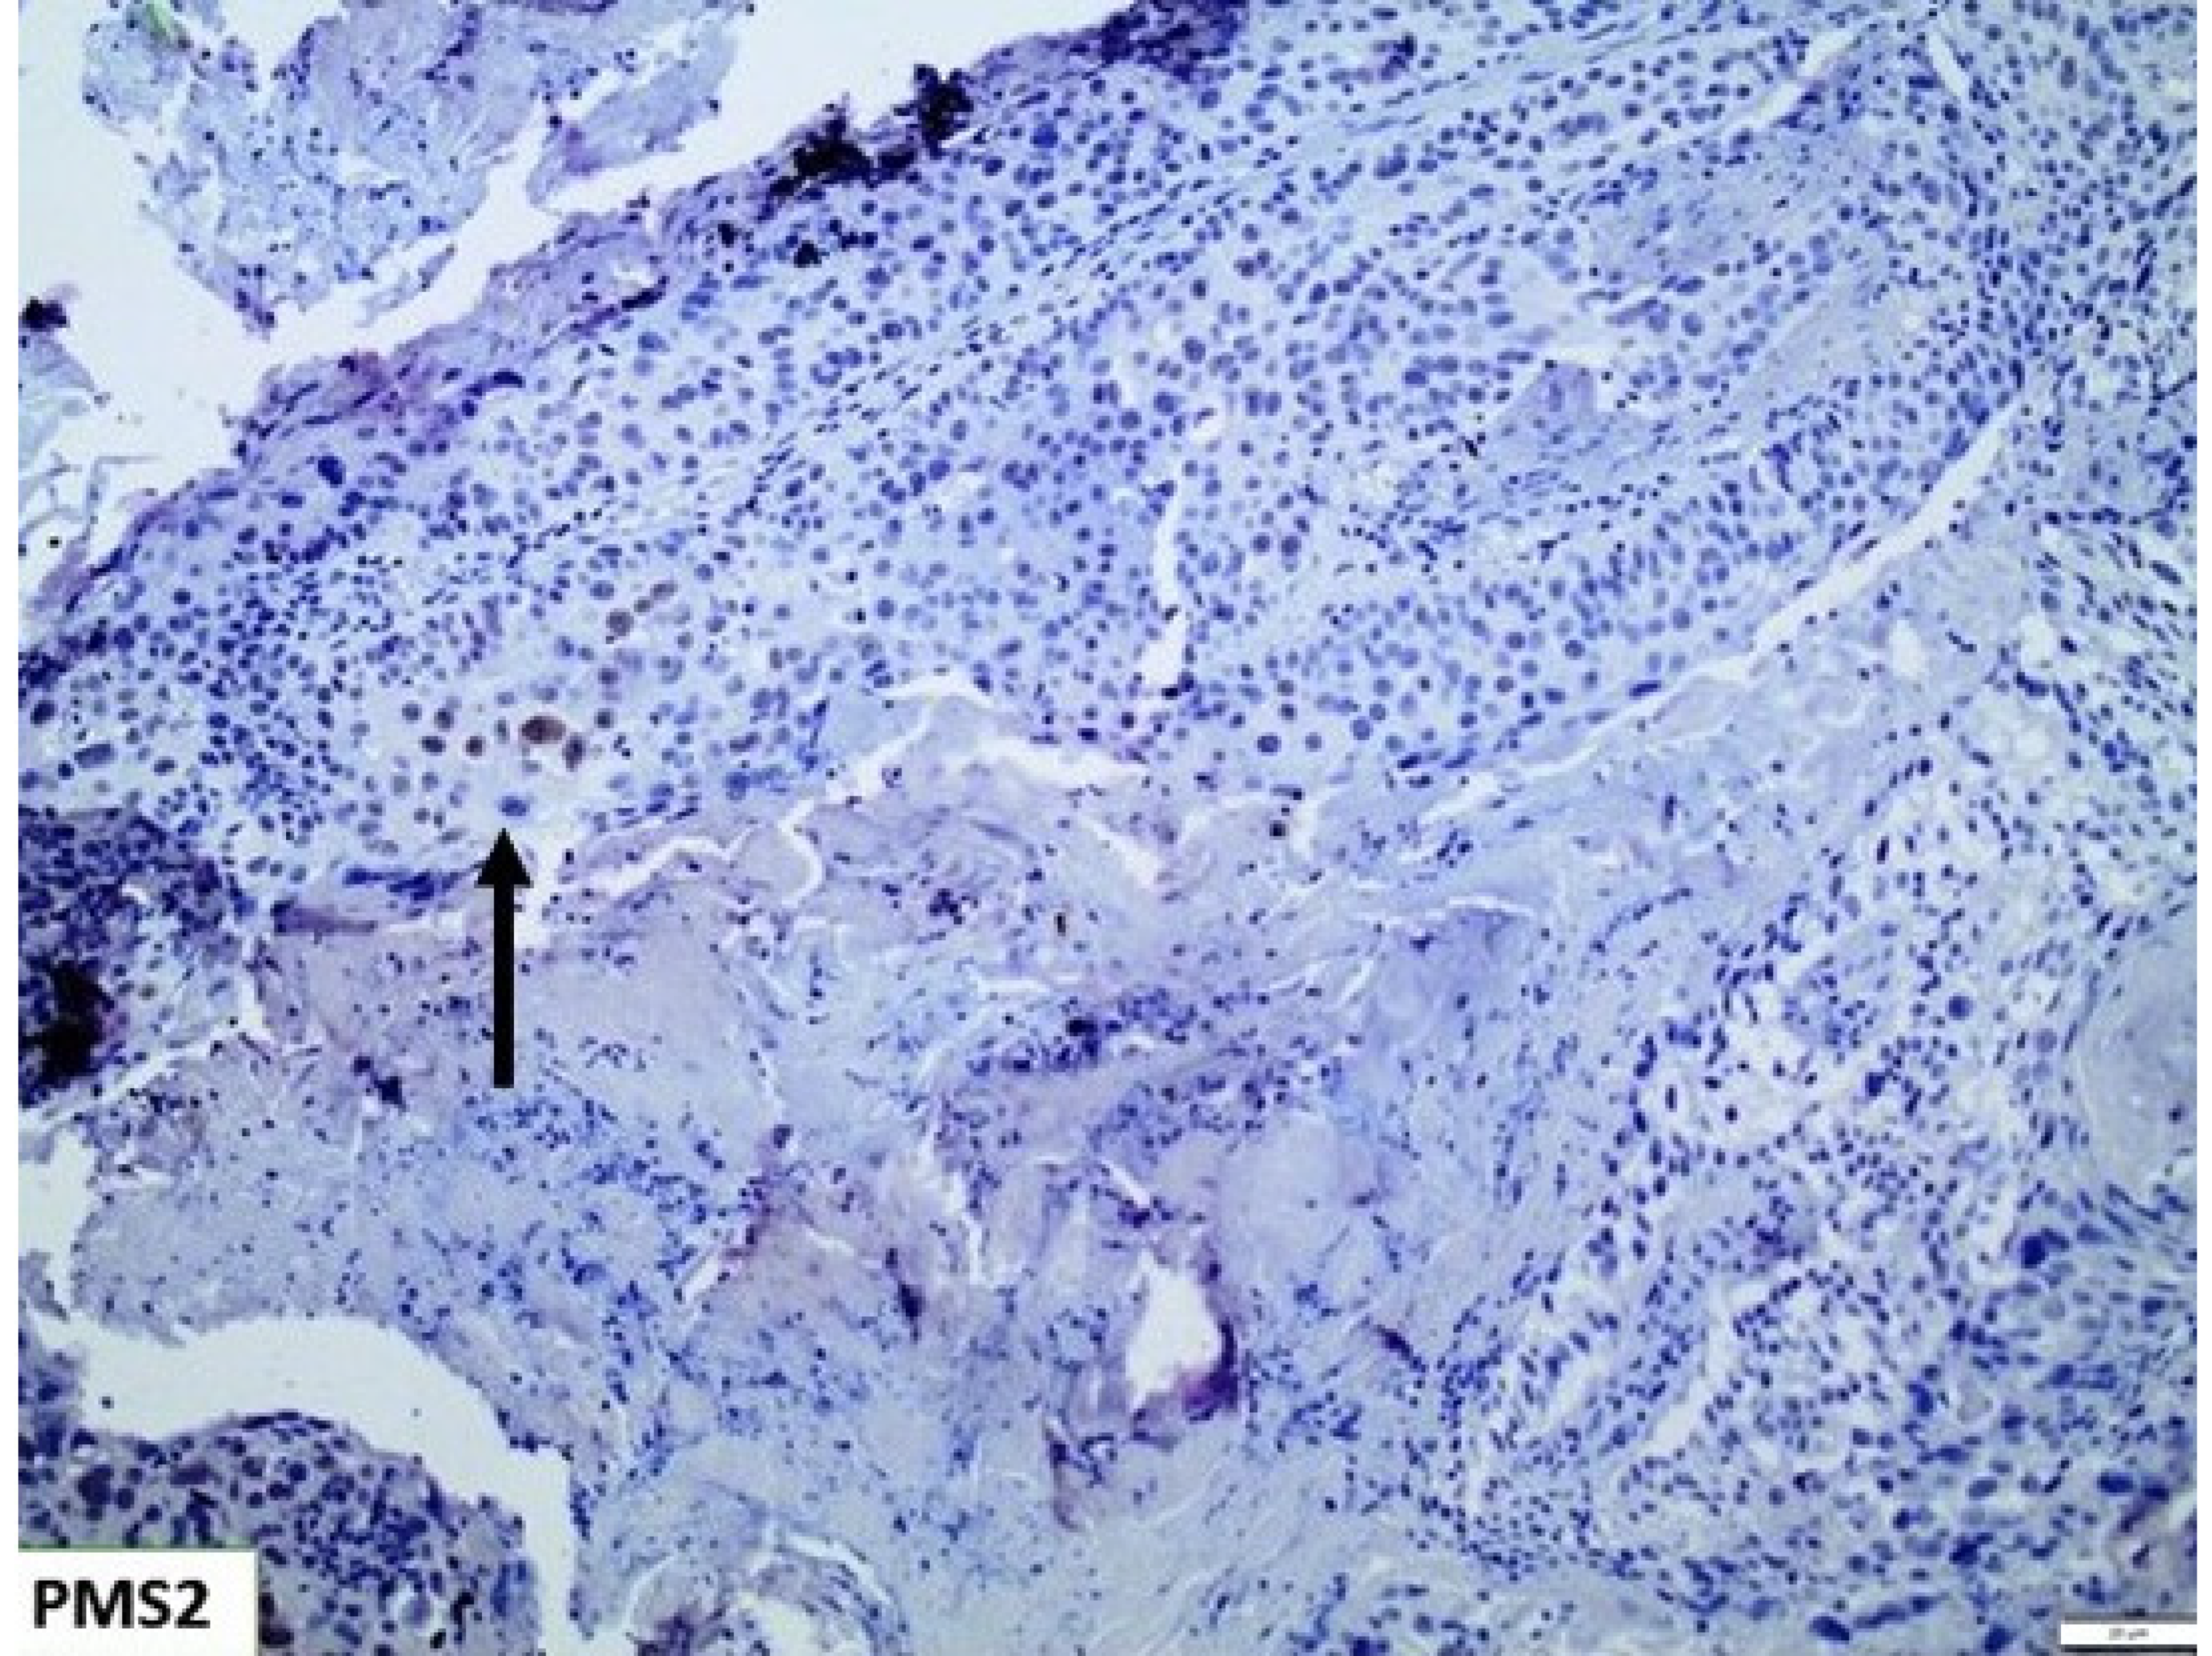

3.2. Mismatch Repair Deficiency (MMR-d)